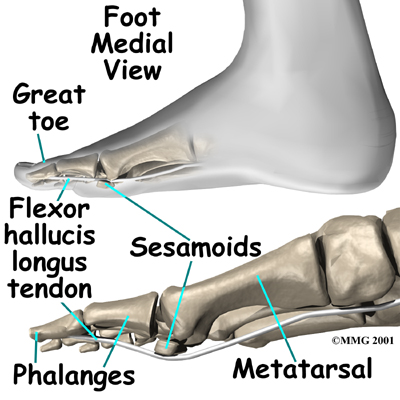

Two pea-sized bones, called sesamoids, are embedded within the soft tissues under the main joint of the big toe. Even though they are small in size, the sesamoids play an important role in how the foot and big toe work. If the sesamoids are injured, they can be a source of severe pain and disability.

The main joint of the big toe forms the inside edge of the ball of the foot. The two small are located on the underside of this joint. There is of the base of the big toe.

The muscles that bend the big toe down (the toe flexors) pass underneath the main joint of the big toe, crossing over the bump formed by the sesamoid bones. This bump acts as a fulcrum point for the toe flexors, giving these muscles extra leverage and power. The sesamoids also help absorb pressure under the foot during standing and walking, and they ease friction in the soft tissues under the toe joint when the big toe moves.